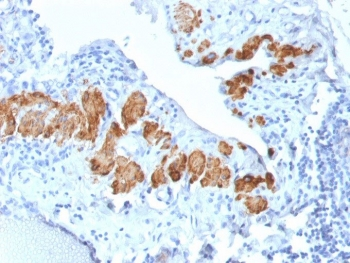

IHC: Formalin-fixed, paraffin-embedded human colon carcinoma stained with SMMHC antibody (MYH11/923).